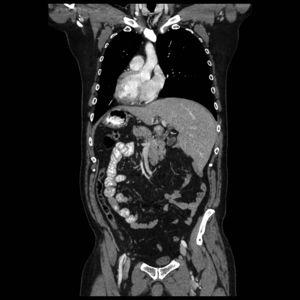

The patient is a 57-year-old male with recurrent respiratory infections and no digestive symptoms. The thoracoabdominal CT scan (Fig. 1) performed due to his respiratory pathology revealed the incidental finding of a right diaphragmatic hernia associated with complete situs inversus.